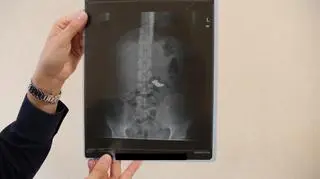

Gdy mundurowi dotarli na miejsce, nie znaleźli jednak przy zatrzymanym dowodu winy. Jak się okazało, mężczyzna połknął łańcuszek. Z pomocą przyszła technologia: dowodem w tej sprawie będzie... zdjęcie RTG.